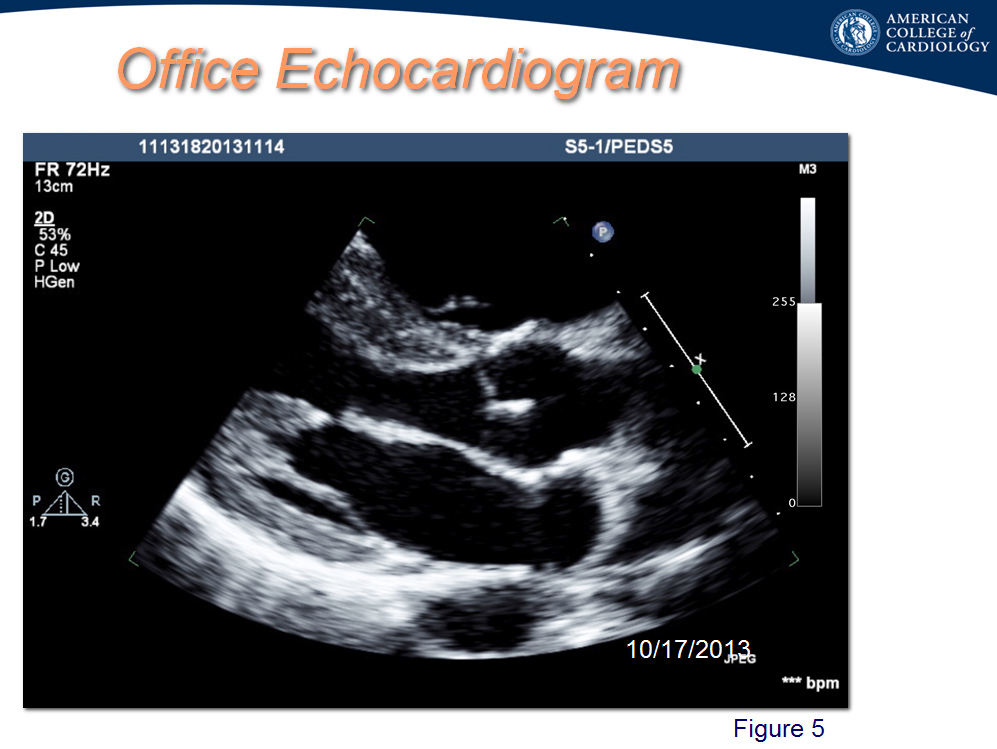

A 17-year-old multi-sport high school athlete and captain of the lacrosse team collapses on the soccer field during active play. The trainer immediately goes to him, identifies him as unresponsive and pulseless, then promptly begins cardiopulmonary resuscitation (CPR) and quickly applies an automated external defibrillator (AED). The tracing (Figure 1) documents ventricular fibrillation. He is shocked three times and has return of circulation. He is admitted to the hospital intubated, undergoes a cooling protocol, and has a full recovery. The hospital electrocardiogram (ECG) and magnetic resonance imaging (MRI) are seen in (Figure 2, Figure 3). The electrophysiologist reports to the family that the diagnosis is commotio cordis, and he is discharged on no medication and without implantable cardioverter-defibrillator (ICD). Two weeks later he undergoes an evaluation with the family requesting cardiac clearance for return to play. His ECG and echocardiogram from the outpatient visit are seen in (Figure 4, Figure 5).

The hospital ECG is post-arrest, and it is common to see prolonged QTc from the cooling, electrolyte abnormalities, or from autonomic changes related to the arrest. One can also see prolongation to QTc in cardiomyopathies.4 The office ECG has a normal QTc (Figure 5). A stress test looking for abnormal QTc at baseline, during exercise, and special attention to the QTc during recovery could support the diagnosis of LQTS. This patient has a stress test that shows a good level of conditioning, a normal QTc at rest and peak exercise, with a prolonged four-minute recovery QTc of 480ms. Such values can be seen in normal patients as well as individuals with long QTc, and "healthy" elite athletes.4-7 He does have ventricular ectopy throughout his stress test and recovery (Figure 6). The observed QTc behavior during stress does not make or rule out the diagnosis of LQTS. For this athlete, enlarged RV on MRI, an epsilon wave in V1, along with T-wave inversion in V1-V3 are more suggestive of ARVC, making answer F the better choice.